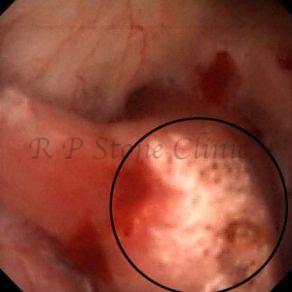

Kidney stone is a solid mass of CRYSTALS. It is the process of crystallization which initiates the formation of kidney stones. This happens in nephrons or units of kidney. Once a small crystal is formed, it can both grow & unite with other crystals leading to the formation of small concretion which eventually forms a stone. Once these large crystals detach from the collecting ducts, the process of stone formation starts in the renal collecting system. A recurrent kidney stone former is advised to know a little bit about something known as Randall’s plaque. Alexander Randall discovered plaques on the renal papillae eight decades back based on examination of 1154 pairs of autopsied Kidneys. He described these renal papillary lesions as cream colored or milk patch areas composed of calcium phosphate & calcium carbonate. These plaques could act as NIDUS for formation of KIDNEY STONE. Calcium Oxalate stone can form on this nidus & then detaches from this plaque to become a free floating stone in the collecting system of kidney

These images are taken as snap shots from the video recording of RIRS Surgery done at our hospital. These are Randall’s Plaques seen with Digital FLEX XC & Digital FLEX XC S. The cream or whitish patches are seen on the tips of RENAL PAPILLAE as seen in images below.

Randall’s Plaques may lead to the formation of Stones.

Those kidney stone patients who have Randall’s Plaques in their kidneys are more likely to form stones again (Recurrent Stones).